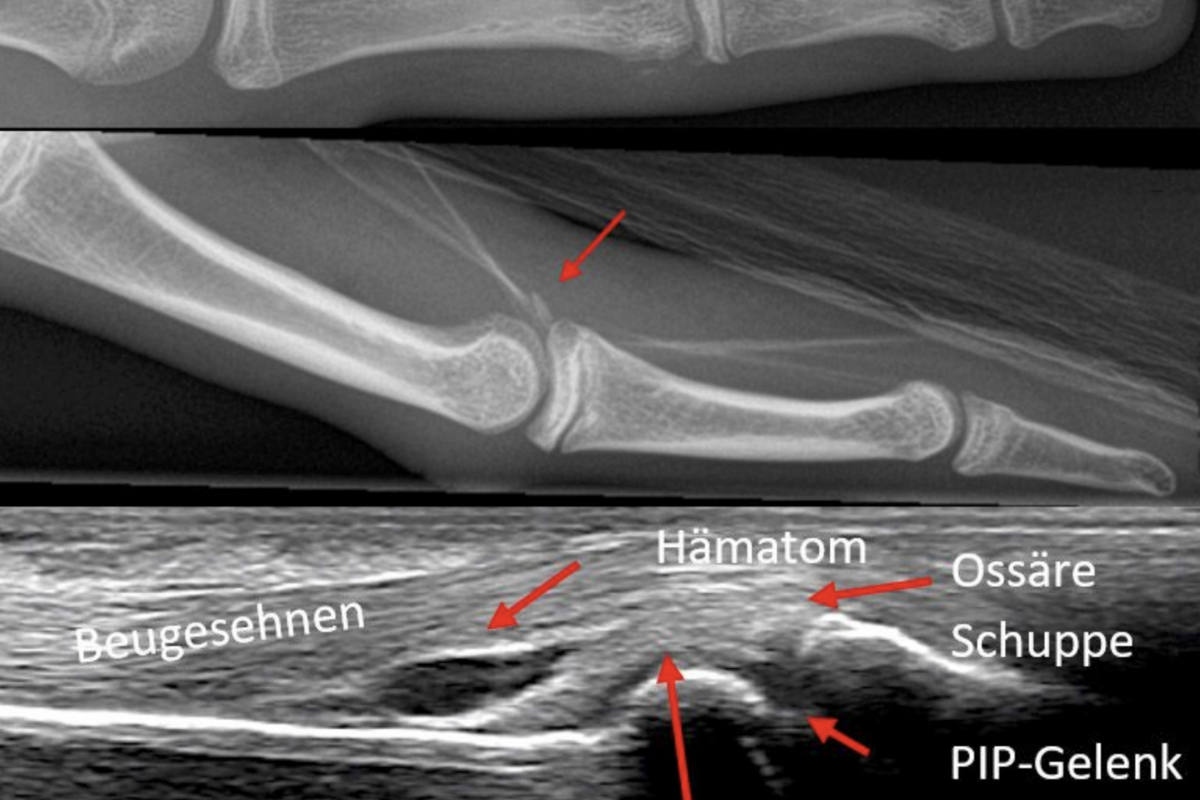

Early on, the IML lauchend «lighthouse projects» that continue to play a central role in digital learning today. Under the common product line Surf – inspired by surfing the World Wide Web, a series of specialised modules were created: CliniSurf, RadioSurf, HemoSurf, DentoSurf, and UroSurf. Over the years, these have become key players in medical e-learning. They provide students and medical professionals with in-depth insights into clinical processes, imaging procedures or medical conditions - always at the forefront of didactics and technology.